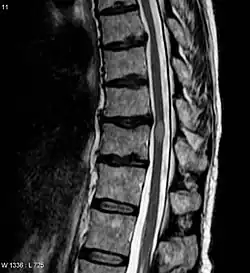

| Acute myelitis | intramedullary lesion > 3 contiguous segments, or spinal atrophy ≥ 3 contiguous segments |

The clinical course and the response to therapy is different for various diseases classed within these groups, showing a better prognosis for those in the NMO-Ab(−)/MOG-Ab(−) group, and a worse prognosis for those in the NMO-Ab(+)/MOG-Ab(+) group.[30] The MOG-related NMO can be radiologically identified by the conus involvement. Myelin-oligodendrocyte glycoprotein antibody–positive patients were more likely to have conus involvement on spinal magnetic resonance imaging.[31]